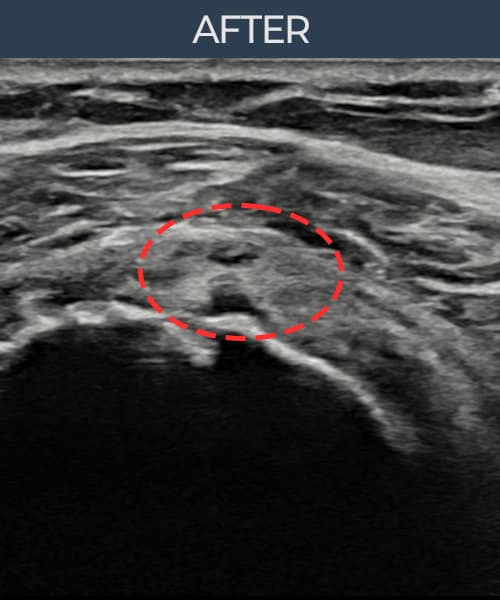

실제 환자의 시술 전후 초음파 영상입니다.

수술 없이 이뤄낸 회복을 직접 확인하세요.

모든 초음파 영상은 실제 환자의 동의를 받아 게시하였습니다. 개인차가 있으며 동일한 결과를 보장하지 않습니다.